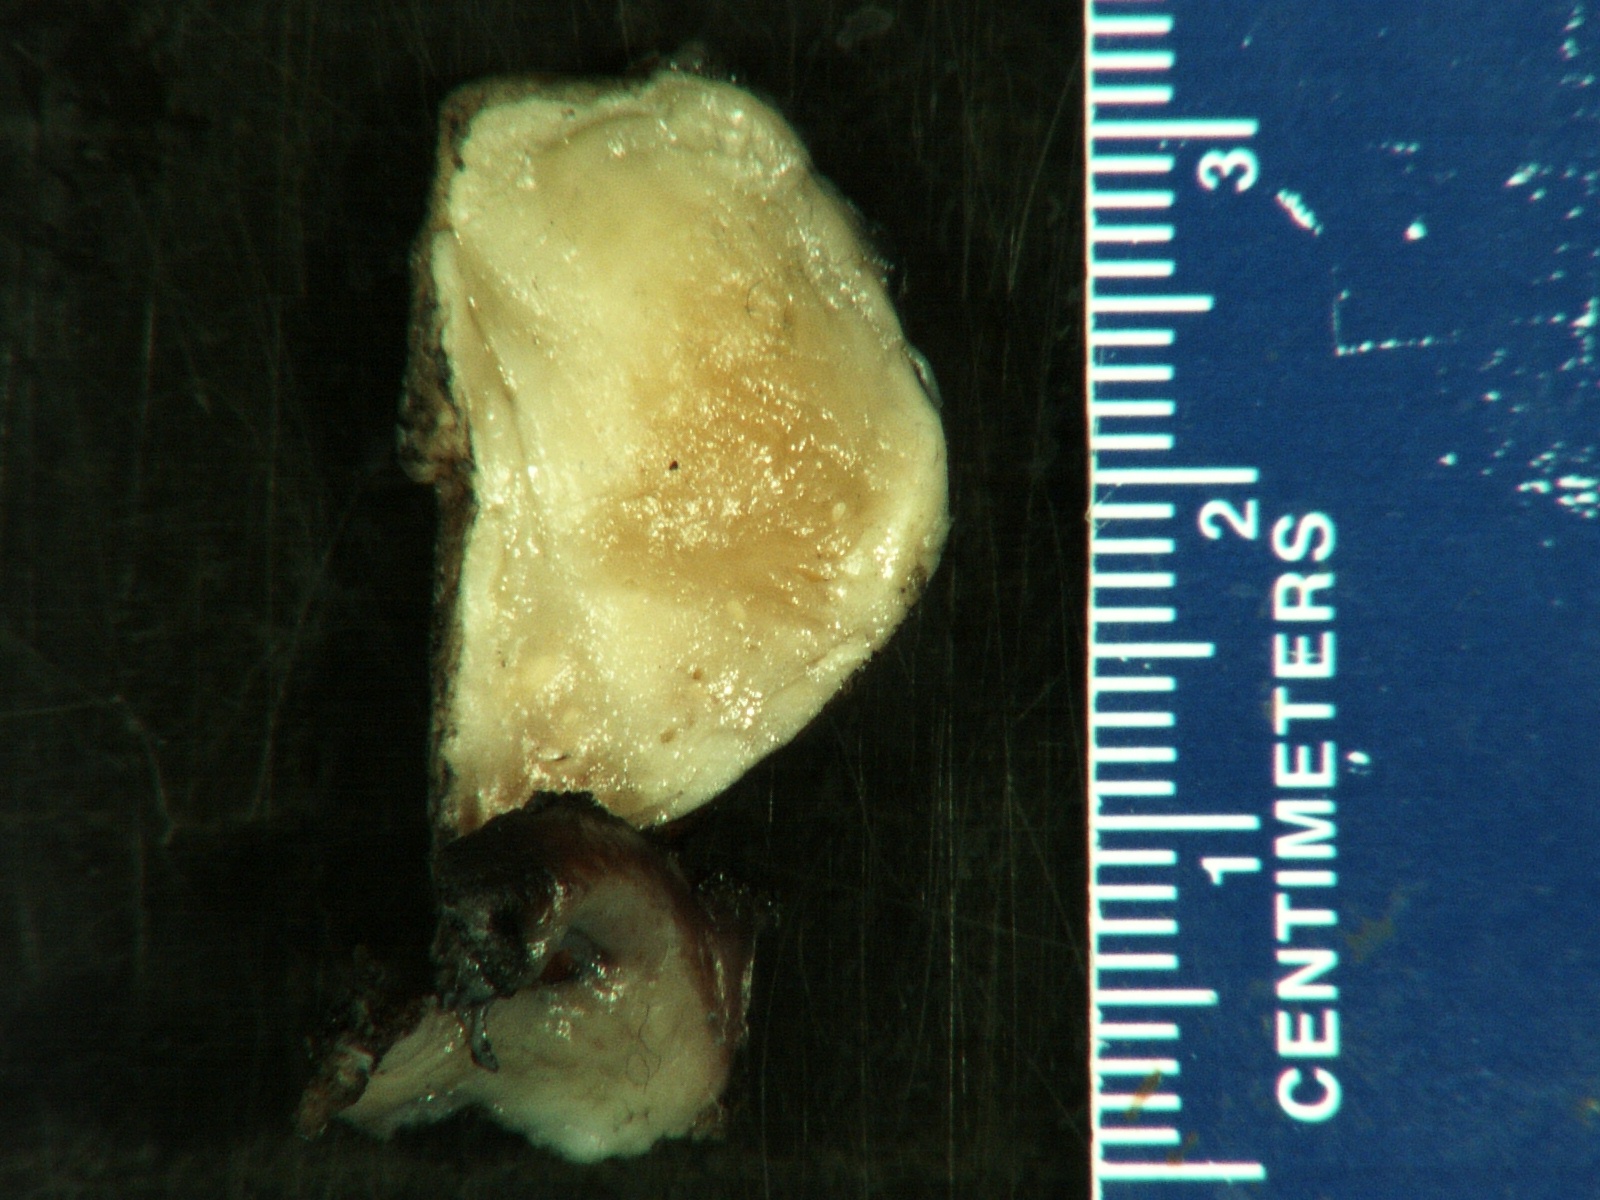

Gross description

- More homogeneous and mature appearance than neuroblastoma

- Varies by subtype, from circumscribed ovoid mass to large multilobulated tumor

- Stroma rich, nodular subtype: area(s) of stroma poor, immature tumor are usually hemorrhagic with well defined borders (J Natl Cancer Inst 1984;73:405)

- Calcification (chalky white, yellow areas) and cystic degeneration may occur

- If large, adrenal gland may be difficult to identify

Gross images